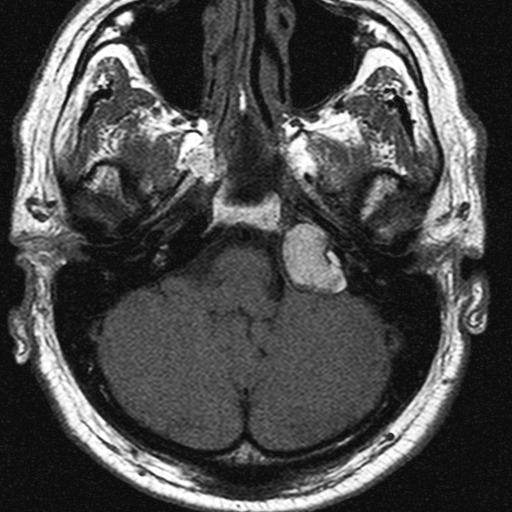

To evaluate soft tissue pathology, mucosal thickening and fluid accumulation, MRI is recommended, especially in the middle and inner ear. MRI plays an important role in inflammatory and tumorous processes, and in their intracranial and extracranial complications. MRI is the modality of choice to assess extracranial and intracranial complications of inflammatory ear disease, including most commonly epidural and cerebral abscesses and sinus thrombosis secondary to chronic otitis media. Examination of the pontocerebellar angle in sensorineural hearing loss is performed by a special thin-slice T2W MRI sequence and postcontrast T1W MRI, since these sequences are capable to detect acoustic neurinoma, while HRCT cannot visualize this abnormality. In some complex diagnostic cases both CT and MRI are needed for accurate diagnosis.

1. image: Patient with sensorineural hearing loss and tinnitus. MR-study (T2, precontrast T1 and postcontrast T1) reveal a mass in the left pontocerebellar angle without significant contrast enhancement. HRCT proves that the mass arises from the petrous pyramid, suggesting cholesterol granuloma. (Asklepios Klinik Altona, Hamburg)